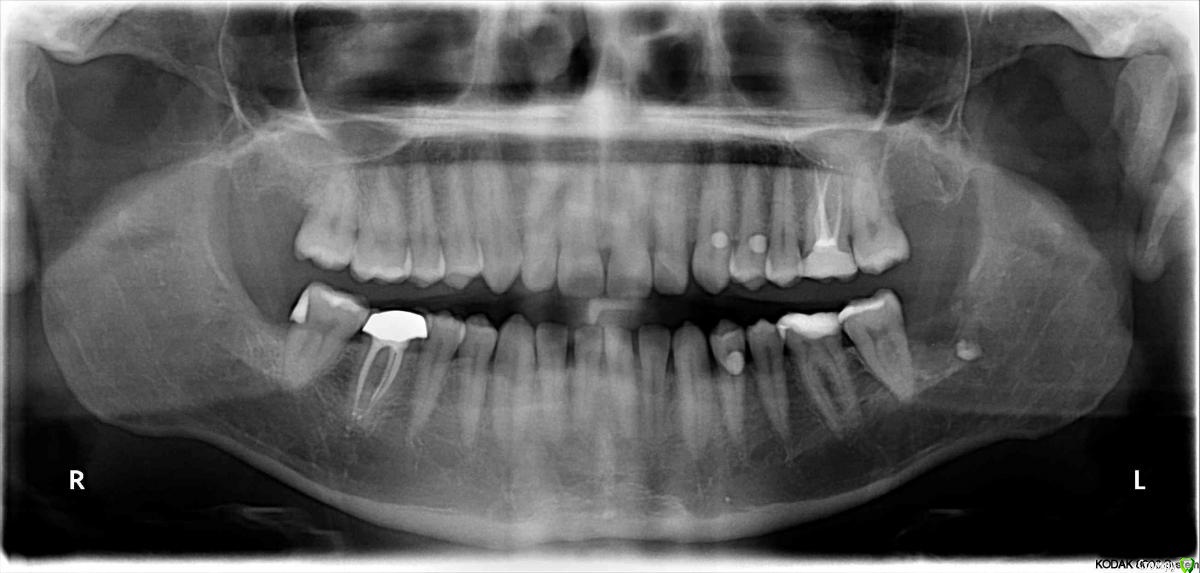

grizli81 Опубликовано 26 октября, 2016 Автор Поделиться Опубликовано 26 октября, 2016 Просто переделать работу Спасибо за ответ. Также прикладываю полный снимок. Ссылка на комментарий

IvanK Опубликовано 26 октября, 2016 Поделиться Опубликовано 26 октября, 2016 на 26 пломба с проблемой, лучше коронку на него28,38,48 - удалять37, 35, 47.... снимок не очень хорошего качества... Ссылка на комментарий

grizli81 Опубликовано 26 октября, 2016 Автор Поделиться Опубликовано 26 октября, 2016 на 26 пломба с проблемой, лучше коронку на него28,38,48 - удалять37, 35, 47.... снимок не очень хорошего качества... 26 - 'это не пломба, а керамическая вкладка. 48 уже удалили. 28 и 38 в пятницу иду Ссылка на комментарий

IvanK Опубликовано 26 октября, 2016 Поделиться Опубликовано 26 октября, 2016 26 - 'это не пломба, а керамическая вкладка. это ничего не меняет Ссылка на комментарий